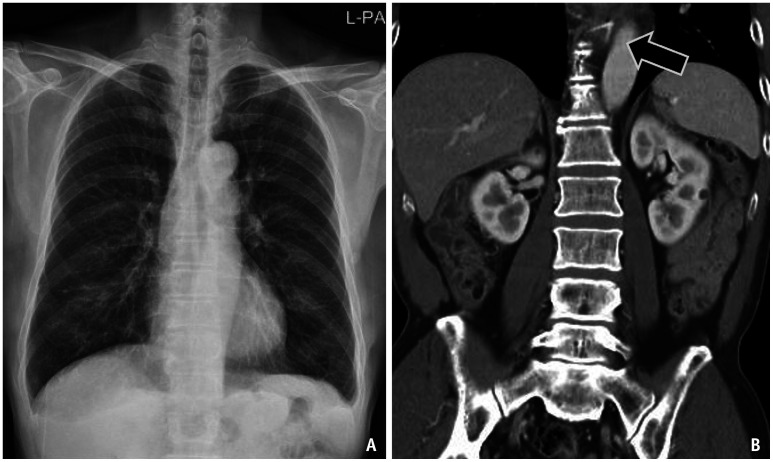

异物摄入和感觉是常见的临床情况遇到急诊和门诊设置。真正的异物摄入通常包括吞咽异物的历史,通常通过x线检查证实。异物摄入的处理取决于异物的类型、大小和位置,以及患者的症状。高风险物体,如钮扣/盘状电池、多个磁铁和尖锐物体,通常需要紧急或紧急内镜切除,以防止穿孔、阻塞和瘘管形成等严重并发症。影像学对诊断和治疗至关重要,x线片是一线方式,CT在检测放射性物体和并发症方面具有卓越的灵敏度。即使没有实际的异物存在,异物摄入和感觉的模拟者也会出现在运动障碍(如贲门失弛缓症)、结构或粘膜异常(如Zenker憩室、反流性食管炎和食管狭窄)和外源性压迫。虽然这些模仿者产生相似的症状,但它们需要不同的诊断方法。本文综述了各种异物的影像学表现、处理策略以及其模仿物的特征,强调了及时准确区分的重要性,以指导适当的干预和改善患者的预后。

Foreign body ingestion and sensation are common clinical conditions encountered in emergency and outpatient settings. True foreign body ingestion typically involves a history of swallowing a foreign object and is often confirmed by radiographic findings. The management of foreign body ingestion depends on the type, size, and location of the object, as well as the patient's symptoms. High-risk objects, such as button/disk batteries, multiple magnets, and sharp objects, often require urgent or emergent endoscopic removal to prevent severe complications such as perforation, obstruction, and fistula formation. Imaging is crucial for diagnosis and management, with radiographs being the first-line modality and CT offering superior sensitivity for detecting radiolucent objects and complications. Mimickers of foreign body ingestion and sensations, even without the presence of an actual foreign body, arise from motility disorders (e.g., achalasia), structural or mucosal abnormalities (e.g., Zenker's diverticulum, reflux esophagitis, and esophageal strictures), and extrinsic compression. Although these mimickers produce similar symptoms, they require different diagnostic approaches. This review highlights the radiological findings, management strategies for various foreign bodies, and the distinguishing features of their mimickers, emphasizing the importance of timely and accurate differentiation to guide appropriate interventions and improve patient outcomes.